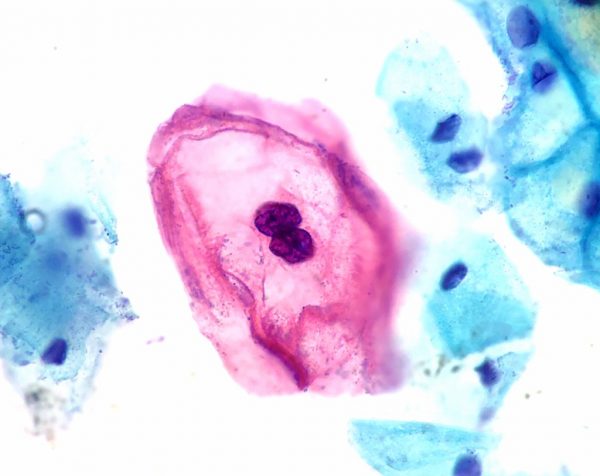

Ιος HPV που δημιουργεί καρκίνο

Ο ιός HPV